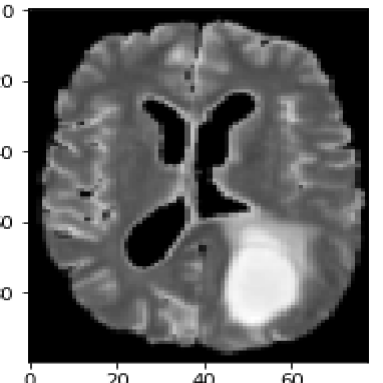

For the second medical example, we use image from the brain tumor segmentation (BRATS) challenge 2015 dataset; see https://www.smir.ch/BRATS/Start2015. The channels in this case consist of contrast-enhanced T1-weighted (T1c), T2 and fluid attenuated inversion recovery (FLAIR) images. Channels contain complementary information allowing accurate diagnosis and quantification of tumor growth. The top row in Fig. 7 shows the input images highlighting a different region of the tumor. Again, we exploit the information contained in different sequences by employing them as separate input channels. The proposed method is thus able to use this complementary information to delineate the different tissues and demonstrates solid results for this concrete example from medicine. The fact that the proposed energy functional can be applied directly to the given images, makes it particularly suitable for medical image segmentation.